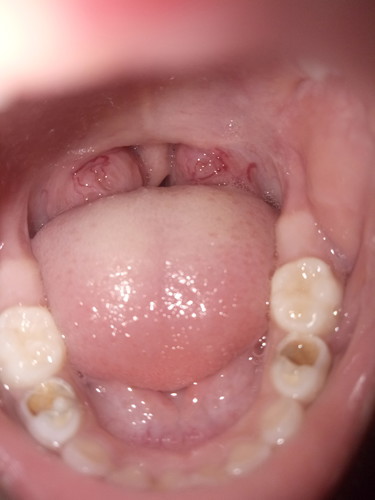

ask lang po normal lang po ba ito.. ung parang halos namamaga ung tonsil po b yan?